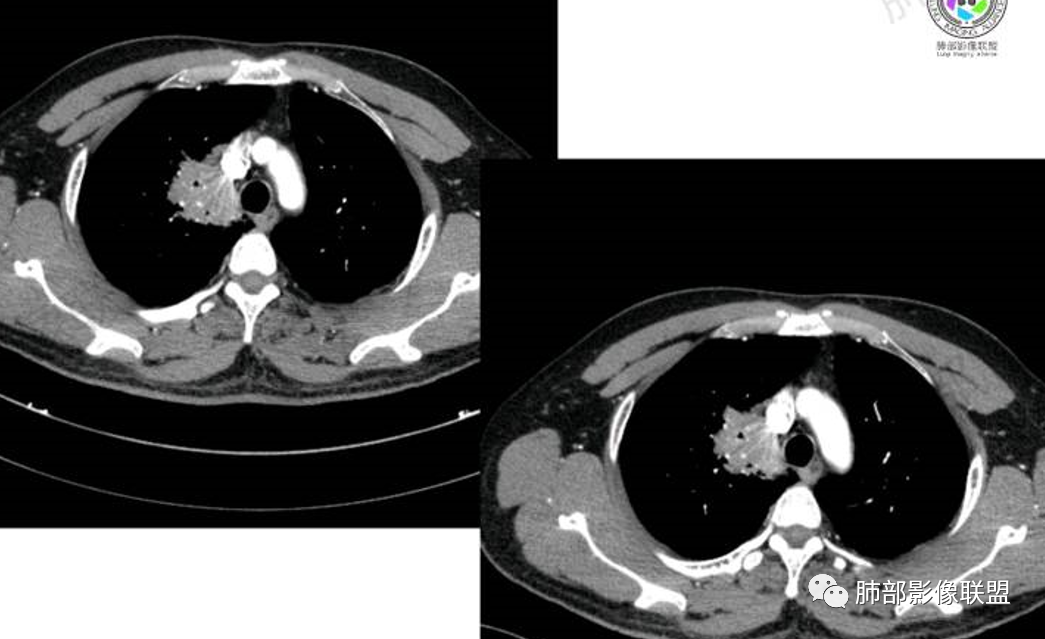

胸部CT:

中年男性,偶有咳嗽,右肺上叶近纵膈旁占位,内可见僵硬的支气管和小空泡征,病灶边缘可见分叶,毛刺,增强病灶中度以上不均匀强化,可见血管造影征,考虑恶性病变,腺癌可能性大。

中年男性,右肺上叶尖段团片病灶,密度均匀,内部支气管充气相,渐进狭窄,强化均匀,血管造影,纵隔侧未见侵犯,诊断:良性,慢性非特异性炎症/机化性炎症,IMT

右肺上叶纵隔胸膜侧一实性肿块,与纵隔胸膜宽基底相连,局部脂肪间隙消失,形态欠规则,内部可见多个小空泡,平扫密度尚均匀,增强后可见点条状强化,内部穿行血管,周围肺组织干净,纵隔淋巴结略肿大,男性44岁,只有咳嗽,考虑恶性肿瘤,腺癌,鳞癌。鉴别结核,OP,炎性假瘤。

右肺上叶近纵膈旁肿块,密度均匀,边缘分叶,毛刺,气管受压变窄,不均匀强化,可见血管造影征,考虑淋巴瘤,鉴别炎性假瘤。

中年男性,右肺上叶纵隔旁软组织肿块,边缘膨隆、毛糙,可见多发分叶,支气管穿行,部分截断,增强后密度欠均匀,纵隔内见多发小淋巴结,首先考虑恶性,腺癌,鉴别淋巴瘤

中年男性,右肺上叶纵隔旁肿瘤,稍膨隆,有毛刺,支气管穿行,远端闭塞,强化均匀,血管走行尚可,考虑淋巴瘤可能性大(支气管远端闭塞,不太符合),鉴别腺癌(气管穿行后闭塞,不太符合),op(病灶稍膨隆)

患者中年男性,咳嗽就诊,无其他不适。胸部CT:右肺上叶尖段上纵膈旁肿块,边界清楚,边缘光滑,内见支气管受压变窄,伴阻塞性改变,增强均匀强化,见血管造影征。综合考虑恶性病变,小细胞肺癌或淋巴瘤。气管镜活检应能明确。

中年男性,右肺上叶纵隔旁实性病灶,边缘有彭隆,有平直,有分叶,有尖角,病灶边缘中心可见支气管征,周围少许磨玻璃,边缘模糊,增强后动脉期病灶可见强化血管影,渐进性强化,临近血管界限清晰。考虑炎性病灶,普通炎性肉芽肿?结核?炎性肌纤维母细胞瘤?鉴别腺癌,淋巴瘤

南边:

病灶紧贴纵隔胸膜

糊墙,胸膜外未见明显侵犯迹象

病灶整体狭长一些

边缘平直、凹陷为主

支气管外侧带的通畅,片内侧带的似乎中近端狭窄,堵塞

内部肺动脉走形还可以

近端支气管壁弥漫增厚

强化均匀

整体炎性的特点比较明显